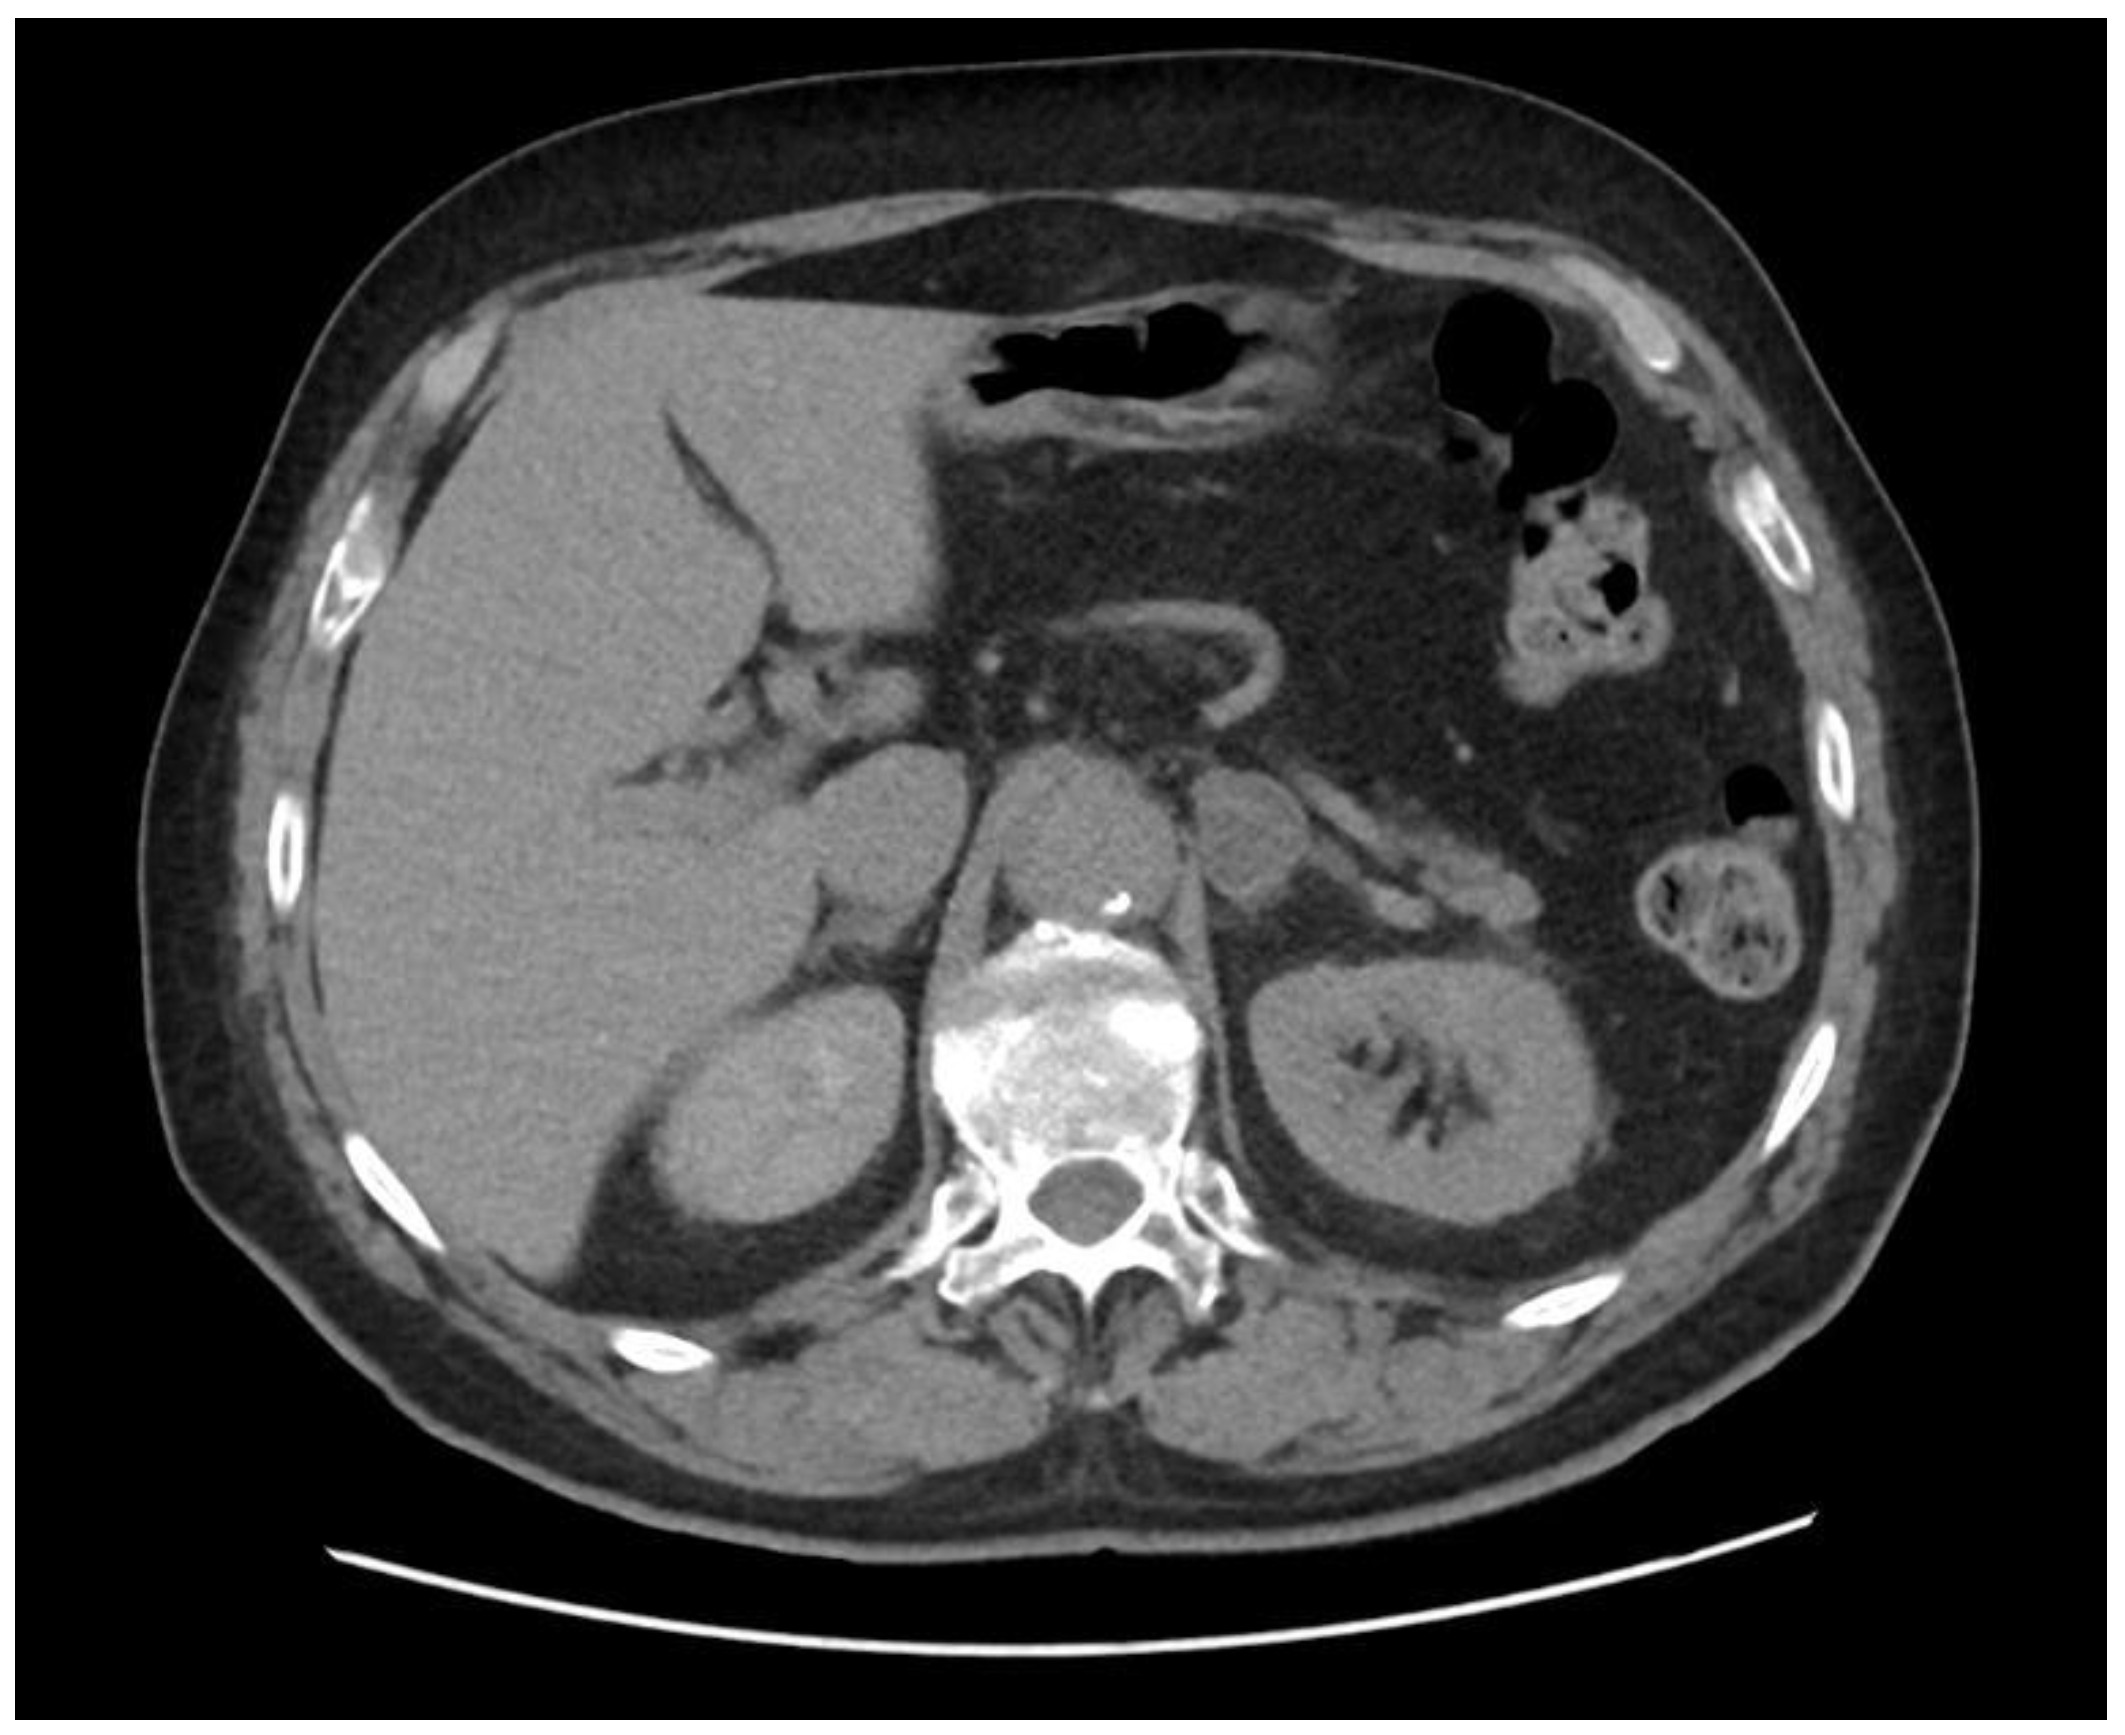

2.3.4. Abdominal Imaging Examination

2.3.5. Carotid-Intima Media Tickness